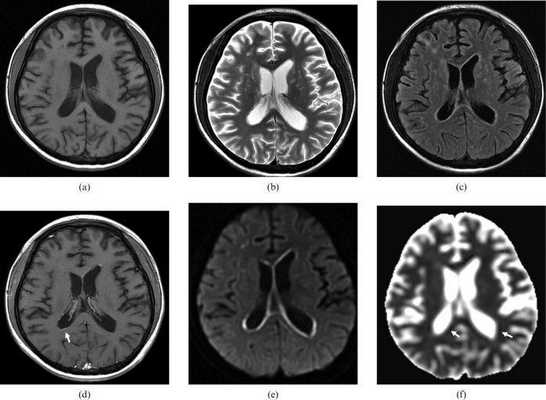

Т1ВИ (а): умеренная дилятация боковых желудочков;

Т2ВИ (b): небольшие округлые гиперинтенсивные очаги в области базальных ядер и субкортикальных отделов белого вещества правой лобной области;

FLAIR изображения (c) подтверждают наличие описанных очагов гиперинтенсивности;

на Т1ВИ после введения контрастного препарата (d) можно увидеть умеренное субэпендимальное контрастное усиление;

DWI и ACD (e,f) определили наличие субэпендимальных областей ограничения диффузии.